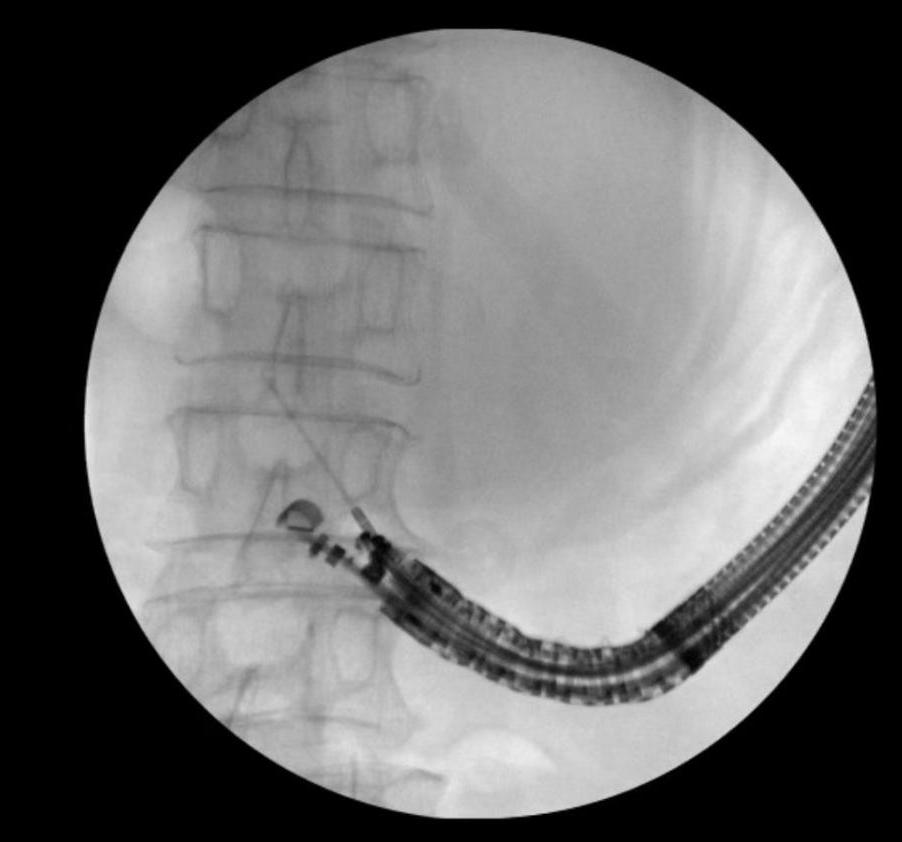

在与患者及家属充分沟通后为其实施“超声内镜引导下胰腺包裹性坏死穿刺引流术+支架置入术”,术中,支架顺利释放,大量褐色囊液涌入胃内。术后复查显示,囊腔明显缩小。

治疗胰腺假性囊肿/胰腺包裹性坏死的方式通常包括保守治疗、外科手术治疗及内镜治疗。保守治疗主要通过药物治疗待其自然吸收,但对于合并感染或假性囊肿增长过大者效果不佳。外科手术治疗是通过各类手术方式建立引流通道,治疗效果确切,但创伤大、并发症多、花费高。内镜治疗主要是针对靠近胃或十二指肠壁的囊肿,在超声内镜引导下穿刺胃/肠壁进入囊腔,置入塑料支架或双蘑菇头金属支架,使囊液引流至消化道内,实现持续引流,直至囊腔闭塞而治愈。当囊肿合并感染时,单纯引流不能达到有效治疗效果,还可通过引流通道行内镜下清创术,并置管引流,可获得与外科手术相当的治疗效果,且创伤更小,并发症少,花费也明显减少。